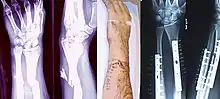

| Internal and external views of an arm with a compound fracture, both before and after surgery | |

Since bone healing is a natural process that will occur most often, fracture treatment aims to ensure the best possible function of the injured part after healing. Bone fractures typically are treated by restoring the fractured pieces of bone to their natural positions (if necessary), and maintaining those positions while the bone heals. Often, aligning the bone, called reduction, in a good position and verifying the improved alignment with an X-ray is all that is needed. This process is extremely painful without anaesthesia, about as painful as breaking the bone itself. To this end, a fractured limb usually is immobilized with a plaster or fibreglass cast or splint that holds the bones in position and immobilizes the joints above and below the fracture. When the initial post-fracture oedema or swelling goes down, the fracture may be placed in a removable brace or orthosis. If being treated with surgery, surgical nails, screws, plates, and wires are used to hold the fractured bone together more directly. Alternatively, fractured bones may be treated by the Ilizarov method which is a form of an external fixator.